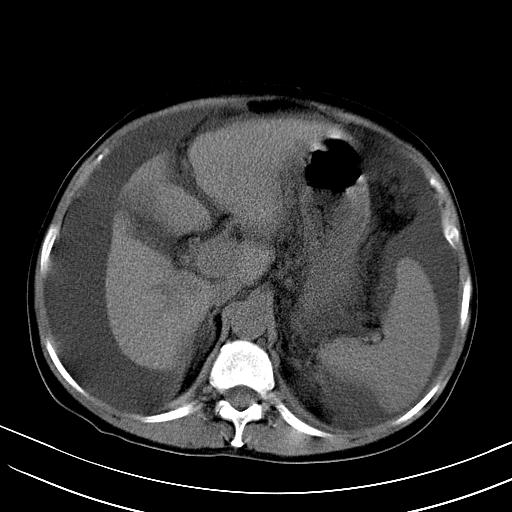

标题: CT23697:肝癌并肝动静脉漏? [打印本页]

标题: CT23697:肝癌并肝动静脉漏?

肝动静脉漏,动脉期肝动脉及门静脉内均可见造影剂……

1)肝右叶肝癌并肝动静脉漏。2)肝硬化,腹水。3)胆囊炎。

肝右叶肝癌并动静脉漏,肝硬化,腹水。

1)肝右叶肝癌并肝动静脉漏 门v右支瘤栓伴海绵样变。2)肝硬化,脾大 腹水。3)胆囊炎。门v高压.

右叶肝癌并肝动静脉漏(动脉期肝动脉及门静脉内均可见造影剂),肝硬化,腹水。(胆囊壁水肿)

1)肝右叶肝癌,考虑并发肝动静脉漏。扫描时间好像慢了。2)肝硬化,门脉高压、脾大、腹水。